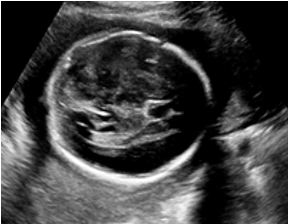

IV-D Experiments on cross-device fetal US

The previous experiment on fetal US images is supported by data restricted to one US imaging device. Here, we evaluate MIDNet for a standard plane classification task on data from different imaging devices (different device domains). Device A is “GE Voluson E8” which is the same device in Sec. IV-C, which acquired 2D fetal US images. Device B is “Philips EPIQ V7 G” which acquired another images sampled from about 500 2D US examinations with gestational ages between 20-32 weeks (see Fig. 2 (b)). In this experiment, we use four different anatomical standard plane locations with sufficient images in both domains, including Abdominal, Brain, Femur and Lips, which are selected by an 10-year-experienced sonographer. In this experiment, the source domain is set as device A while the target domain is device B. Training data consists of all four standard planes from the source domain as well as Abdominal and Brain from the target domain. We aim to separate anatomical features (categorical features) and imaging device features (domain features) to obtain generalized anatomical features for achieving high performance of standard plane classification on (Femur and Lips). Here, contains Abdominal, Brain, Femur and Lips from the source domain and contains Abdominal and Brain from the target domain. Hyper-parameters to in Eq. 11 are for the proposed MIDNet model and is additionally for MIDNet+.